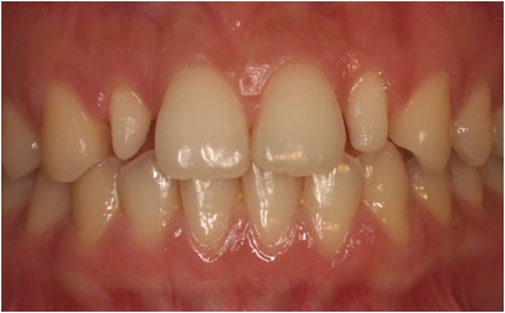

In 1987, Granhene defined peg lateralis as a tooth with an incisal mesiodistal width shorter than the cervical width (Figure 1). The maxillary lateral incisors are often affected, presenting as tapered-shaped teeth, thus giving rise to the name peg lateralis (Davis, 1987). The prevalence of peg lateralis varies from 0.6% to 9.9% depending on ethnicity, sex, and region; Mongolians exhibit a significantly higher prevalence rate than other ethnic groups. According to meta-analyses, the overall prevalence rate is 1.8% (Hua et al., 2013). Although non-syndromic teeth abnormalities are inherited as an autosomal trait, existing literature suggests that peg-shaped teeth are 1.35 times more prevalent in women than in men (Polder et al., 2004). Both unilateral and bilateral peg lateralis seem to have a similar prevalence; however, the frequency of left-side unilateral peg lateralis is almost twice that of right-side ones (Magnusson, 1977; Meskin and Gorlin, 1963).

Figure 1. Peg lateralis on both maxillary lateral incisors.